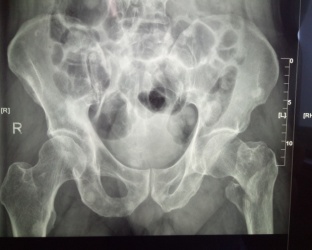

患者馬X,男,87歲,合并糖尿病、腦梗塞。